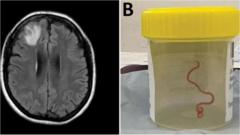

Beyinde canlı solucan bulundu

Dünyada ilk kez, Avustralyalı bir kadının beyninden 8 santimetre uzunluğunda bir solucan çıkartıldı.

“Sicime benzeyen yapı” geçen yıl Canberra kentindeki bir ameliyatta bulundu, ancak ameliyatın raporu bu yıl kamuoyuna açıklandı.

Kaynak, Avustralya Ulusal Üniversitesi

Doktorlar, beyinde canlı solucanı bulduklarında büyük şaşkınlık yaşadılar.

Ameliyatı gerçekleştiren Dr. Hari Priya Bandi “Kesinlikle beklediğimiz bir şey değildi, herkes şoke oldu” dedi.

64 yaşındaki kadında aylar süren mide ağrısı, öksürük, gece terlemesi gibi semptomların ardından, unutkanlık ve depresyon da görüldü.

Ocak 2021’in sonlarında hastaneye yattı ve daha sonra yapılan görüntülemede beynin sağ ön kısmında bir lezyon görüldü.

Ancak bütün bunların sebebi, Haziran 2022’de Dr. Bandi’nin yaptığı biyopsiyle anlaşıldı.

Doktorlar kırmızı parazitin, hastanın beyninde iki ay kadar canlı kalmış olabileceğini söyledi.

Vakanın, dünyada ilk kez insan beyninde larva istilası ve gelişimi olduğu sanılıyor. Uzmanlar bunun hayvanlardan insanlara geçen hastalıklar ve enfeksiyonların oluşturduğu artan tehlikeyi gösterdiğini söylüyor.